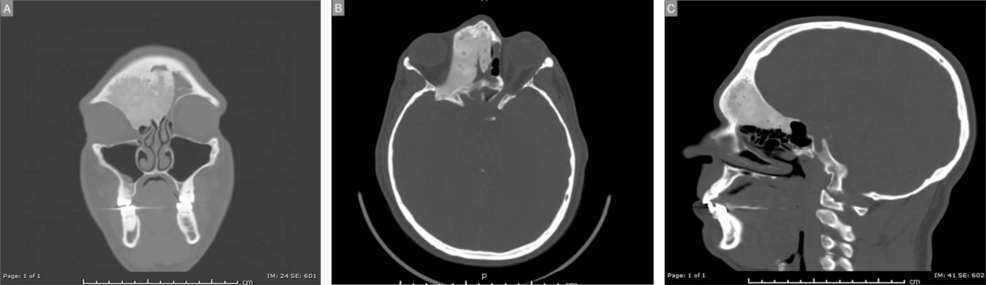

Second, the use of advanced imaging, such as CT scans and MRIs, is essential not just for planning the resection, but for verifying the “watertight” nature of the reconstruction. The absence of a visible pulse during a physical exam does not always signify the reconstruction is sufficient; subtle defects can still lead to long-term complications.